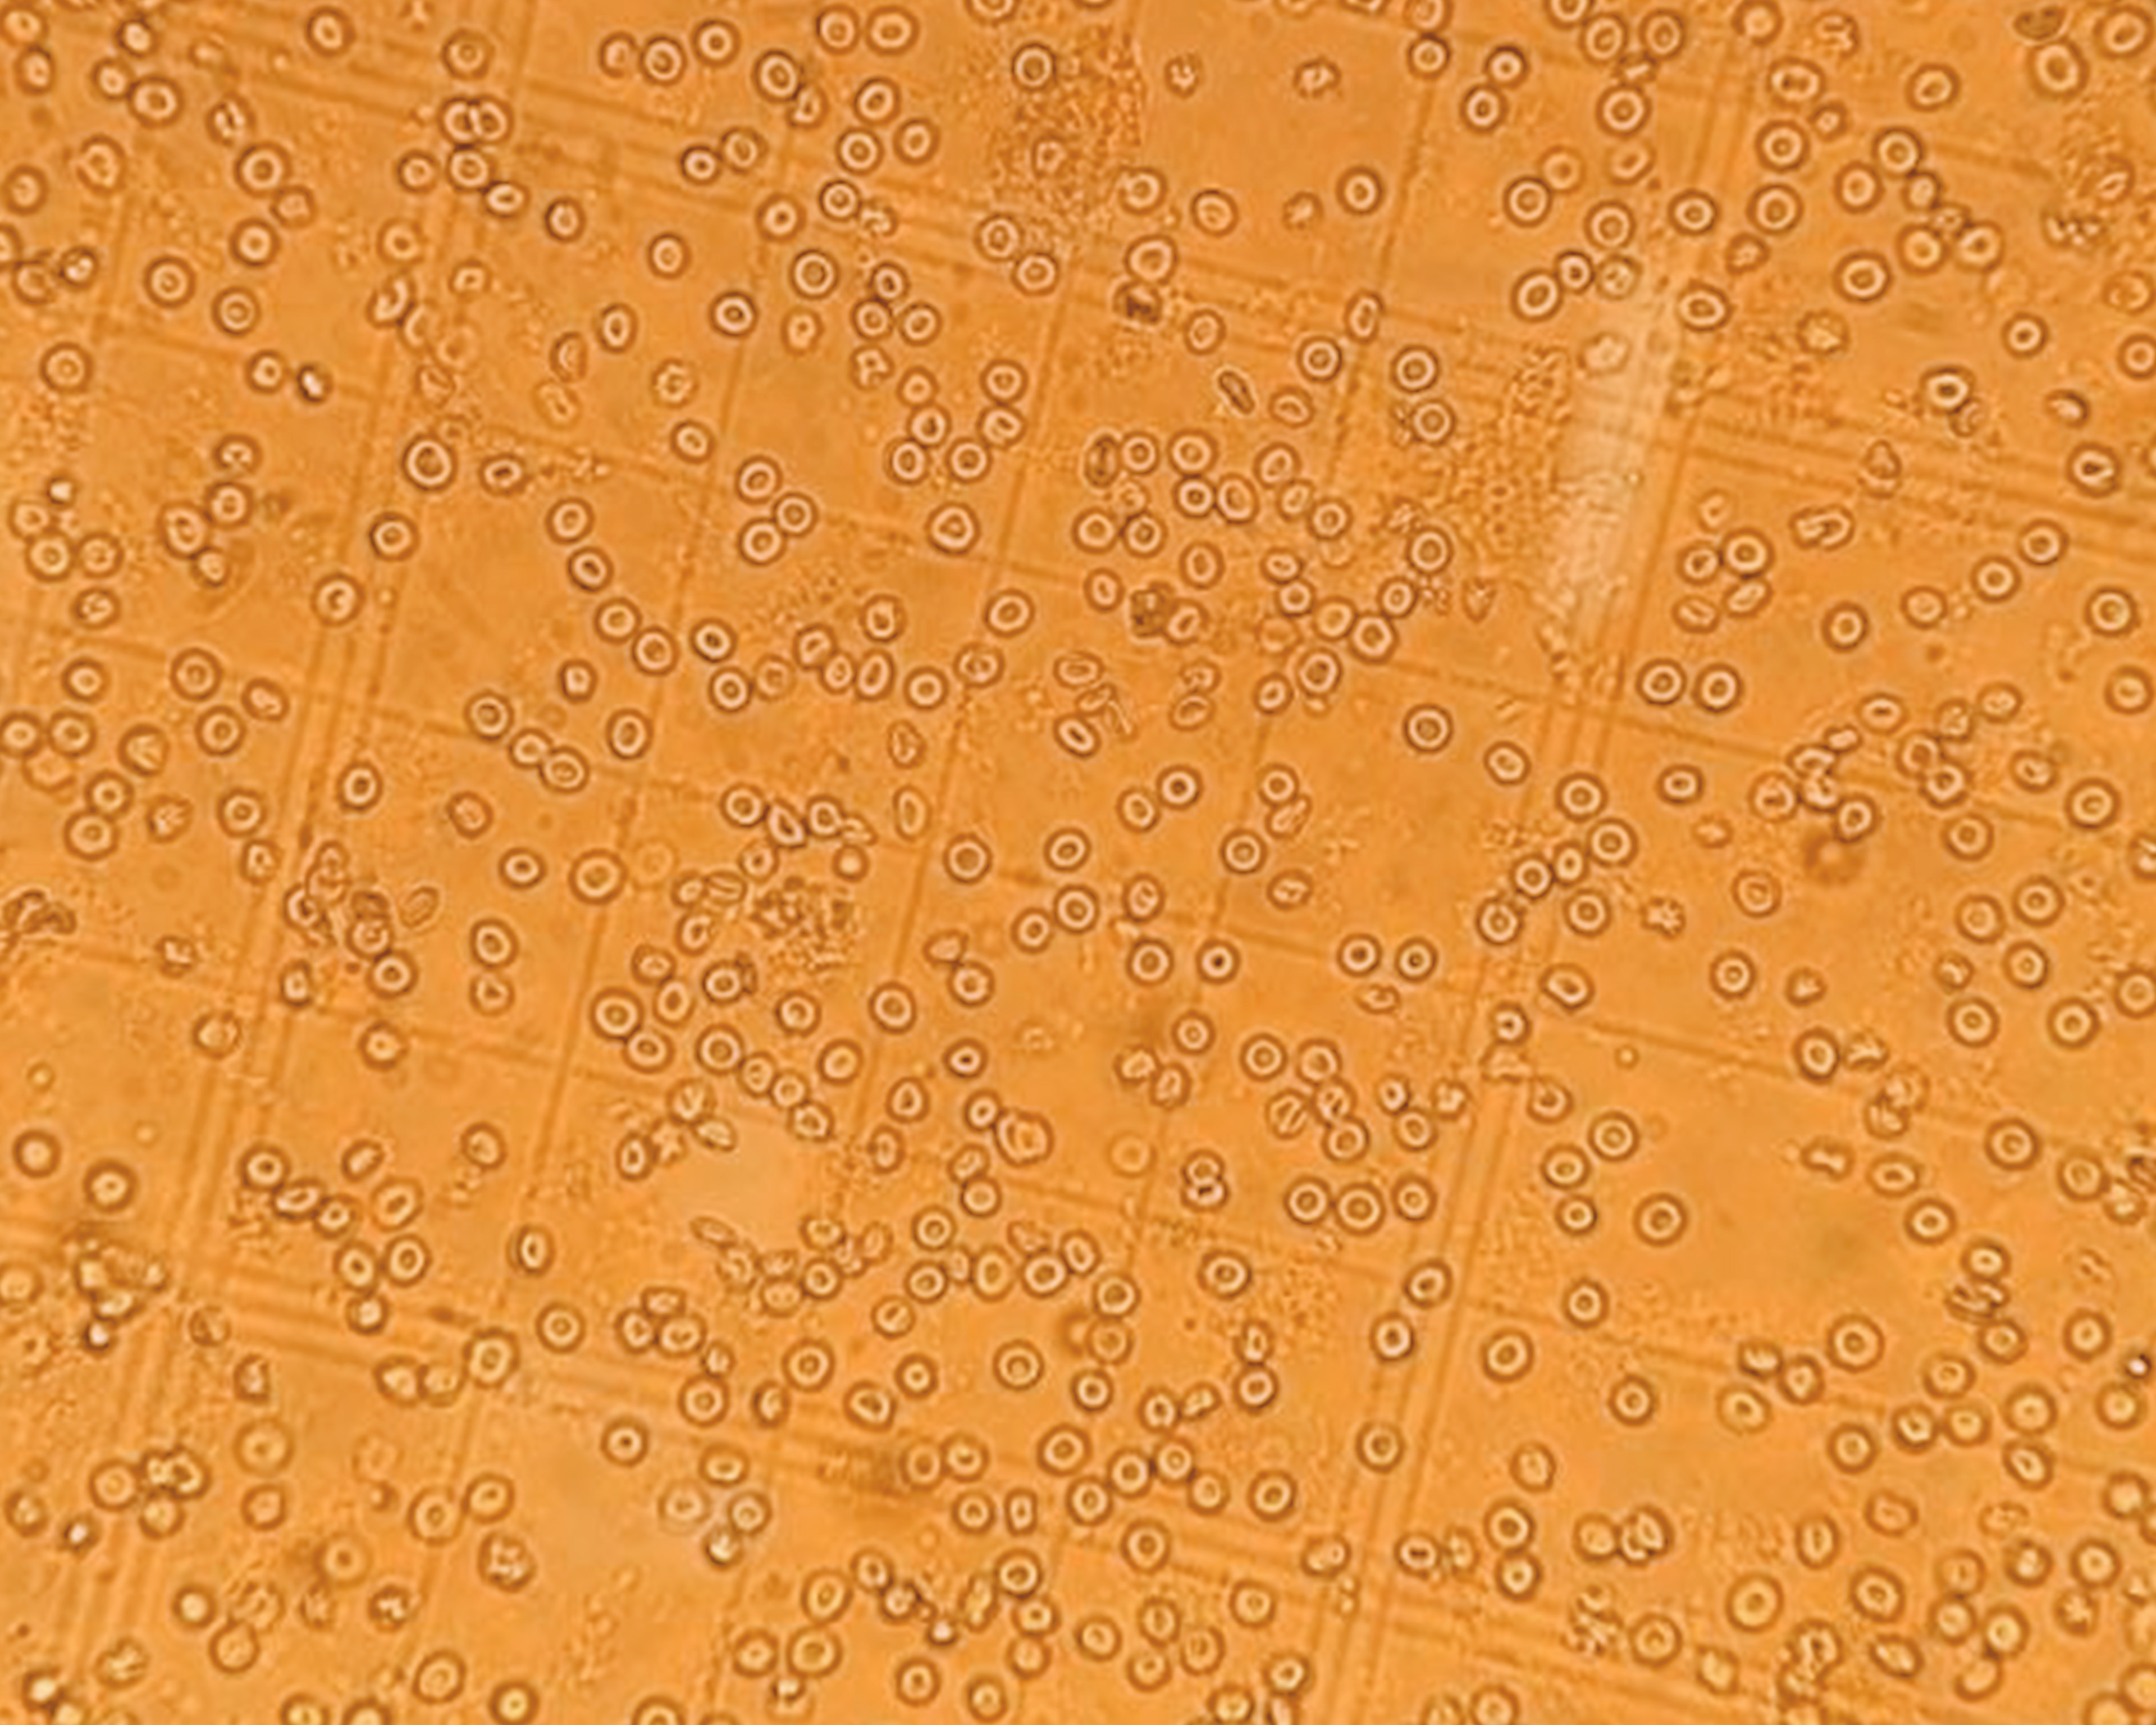

(Q7) The final key question – whether the PROTAC is cell permeable – is answered using cell uptake assay and NanoBRET assay to confirm target engagement.